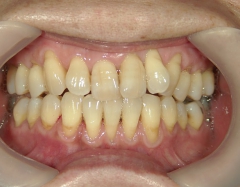

矯正歯科 治療後矯正歯科 プチワイヤー矯正 治療後矯正歯科(プチワイヤー矯正)治療後

矯正歯科 治療後

no.12_5333_治療後_左.jpgno.12_5333_治療後_正面.jpgno.12_5333_治療後_右.jpg

矯正_灰色.pngno.12_5333_治療後_下.jpg矯正_灰色.png